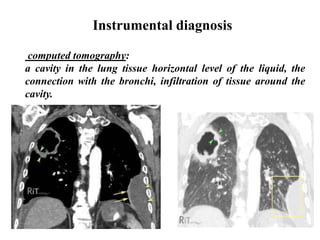

Instrumental diagnosis

computed tomography:

a cavity in the lung tissue horizontal level of the liquid, the

connection with the bronchi, infiltration of tissue around the

cavity.